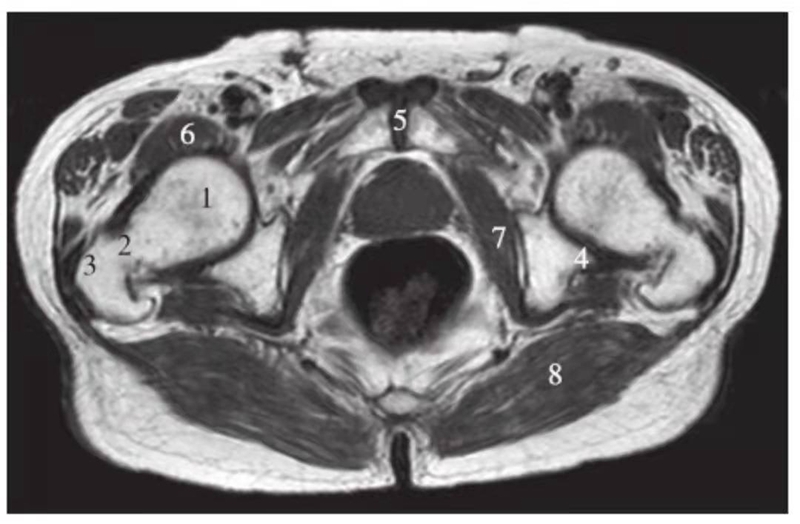

横轴位

正常髋关节经股骨颈层面T1WI像

1.股骨头;2.股骨颈;3.转子间部;4.髋臼后唇;5.耻骨联合;6.髂腰肌;7.闭孔内肌;8.臀大肌